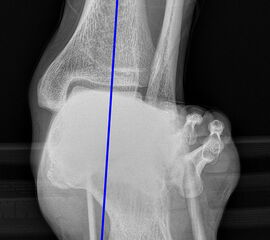

Saltzman Rückfußachsaufnahme (Hindfoot alignment view)

Rückfuß-Alignement-Aufnahmen sind eine wichtige Ergänzung zur Diagnostik von Kalkaneusfehlstellungen (Varus und Valgus), sowie bei der Planung von Rückfußkorrekturen 14.

Indikation:

• Beurteilung der Rückfußachse.

Positionierung:

• Der Patient steht auf einem Podest, beide Beine sind gleichmäßig belastet.

• Die Fußachse ist entlang des Zentralstrahls ausgerichtet.

• Die Röntgenröhre befindet sich dorsal des Beines.

• Röntgenkassette 20° gekippt zur Vertikalen, im 90°-Winkel zum Zentralstrahl.

• Der Zentralstrahl ist von dorsal auf das obere Sprunggelenk fokussiert.

Kennzeichen des Röntgenbildes:

• Markieren der Tibiaachse mit Verlängerung nach distal.

• Der funktionelle Hebelarm des Kalkaneus errechnet sich aus der Distanz zwischen der Tibiaachse und dem am weitesten plantar gelegenen Punkt des Kalkaneus.

• Liegt der tiefste Punkt des Kalkaneus medial der Tibiaachse, handelt es sich um eine Varus-Stellung, liegt er lateral, um eine Valgus-Stellung.

• Norm: Auftrittspunkt 3,2 ± 8 mm medial der Tibiaachse 14.

Zur Vollansicht und zum Lesen der Bildbeschreibung bitte die Bilder anklicken.